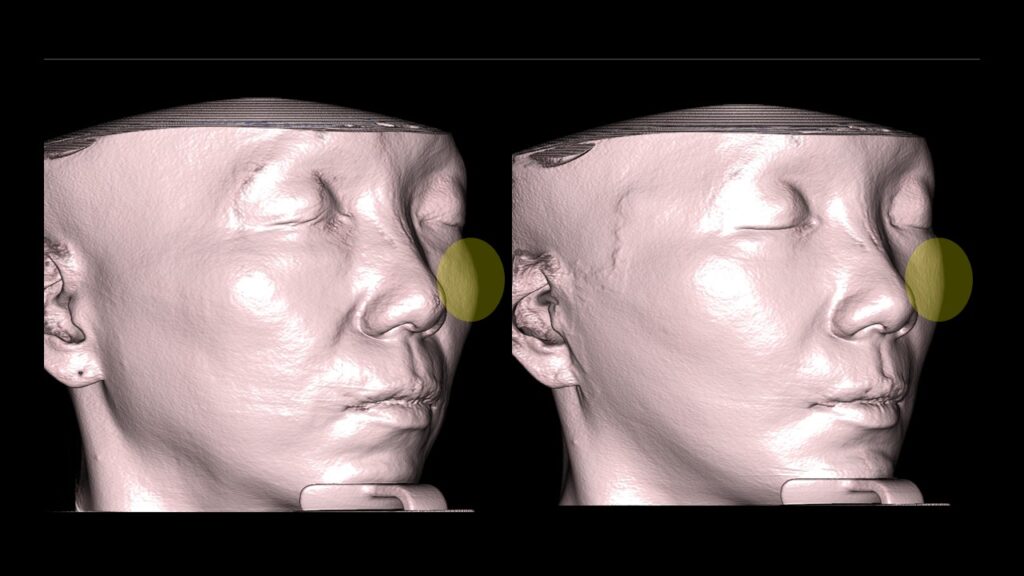

4. Case Studies (3DCT & Medical Photos)

-

Case 1: (Zygoma Reduction + Face Lift) 1-year post-op shows a significant reduction in mid-face width and improvement in nasolabial folds.